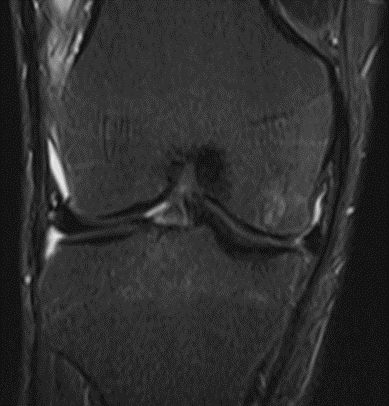

MRI scans illustrating the improvements regarding Group 2 are presented below, showing pre-treatment images with evident cartilage defects, pronounced bone marrow edema, and synovial inflammation, followed by post-treatment scans demonstrating improved joint structure, reduced edema, and decreased inflammation (Figures 12-29).

MRIs of Group 2

Figure 16: Female, 76 years, pre-intervention MRI.

Figure 17: Female of figure 16, two-month follow-up MRI: MSC plus ChondroFiller® liquid.